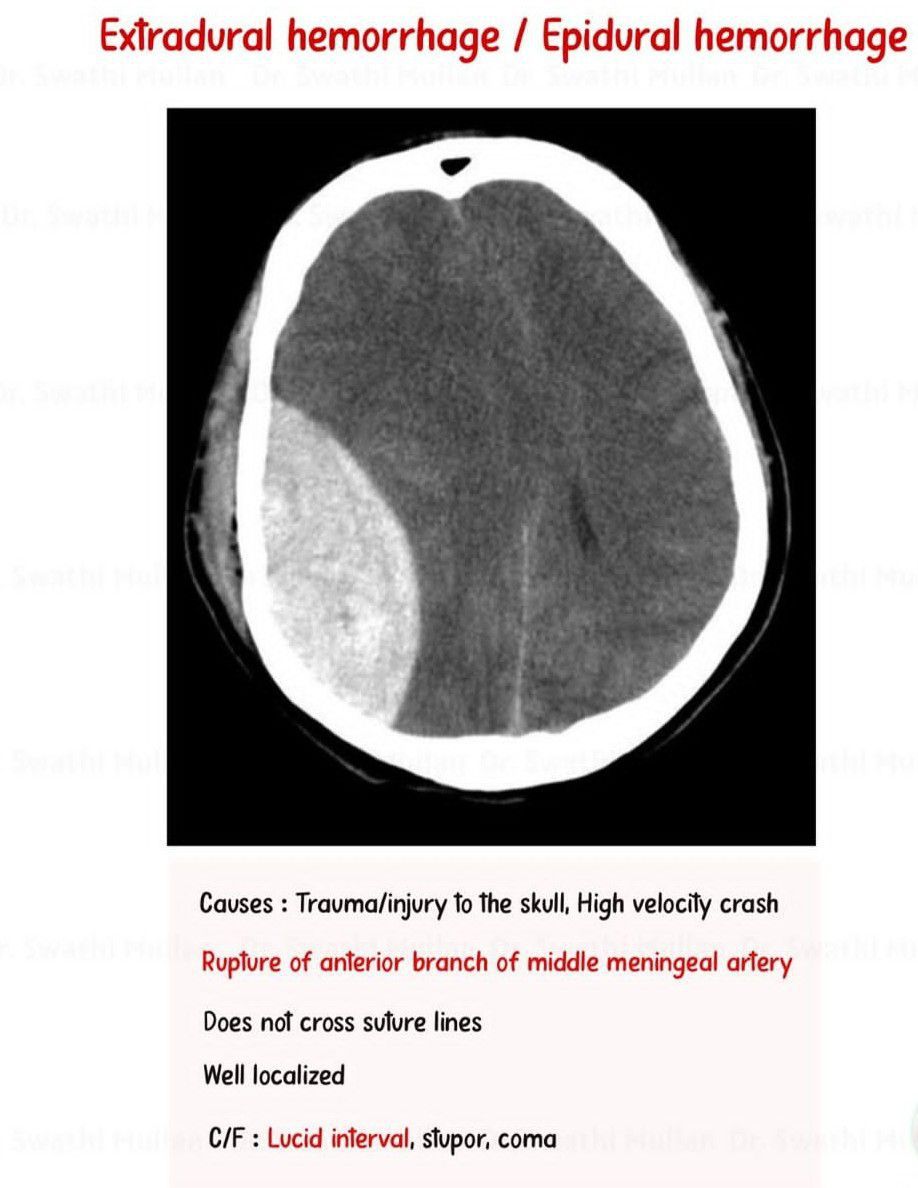

Epidural Hematoma